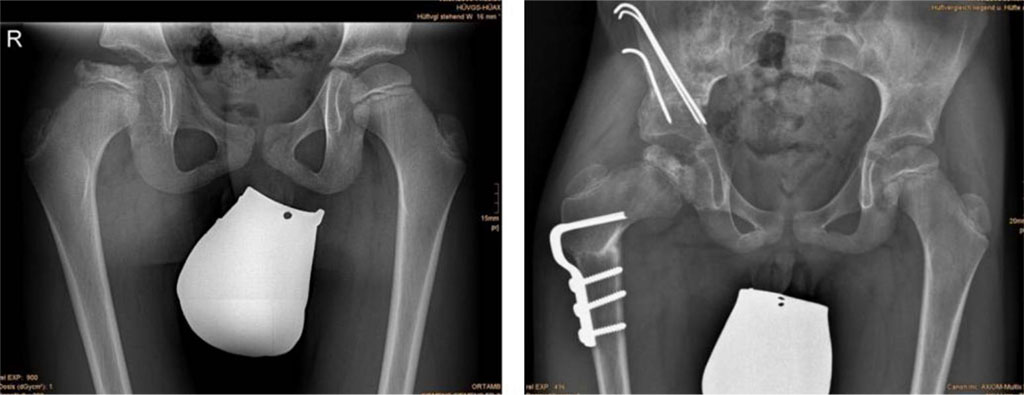

![Fig. 1 Preoperative radiograph showing morphological sequelae of Legg-Calvé-Perthes disease in the left hip - oversized ellipsoid femoral head, GT elevation, shortened femoral neck, and mild acetabular dysplasia [49].](artikel-29-bild-1.jpg)

Fig. 1 Preoperative radiograph showing morphological sequelae of Legg-Calvé-Perthes disease in the left hip - oversized ellipsoid femoral head, GT elevation, shortened femoral neck, and mild acetabular dysplasia [49].